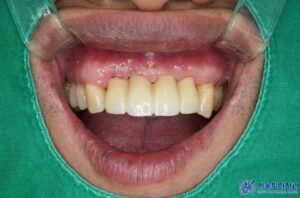

보철물 재제작 후 사진입니다.

제거 후 보철물 제작까지

단 2일 만에 치료를 마무리 하였으며,

환자분께서도 심미적으로

매우 만족해 하셨습니다.

앞니 임플란트 보철물 제작 시에는

기능적인 면뿐만 아니라

심미적인 부분까지 고려해야 합니다.

수정구치과 서울박사치과에서는

맞춤형 지대주와 고품질 보철물을 활용하여

환자분께 꼭 맞는 치료를

해드리고 있습니다.